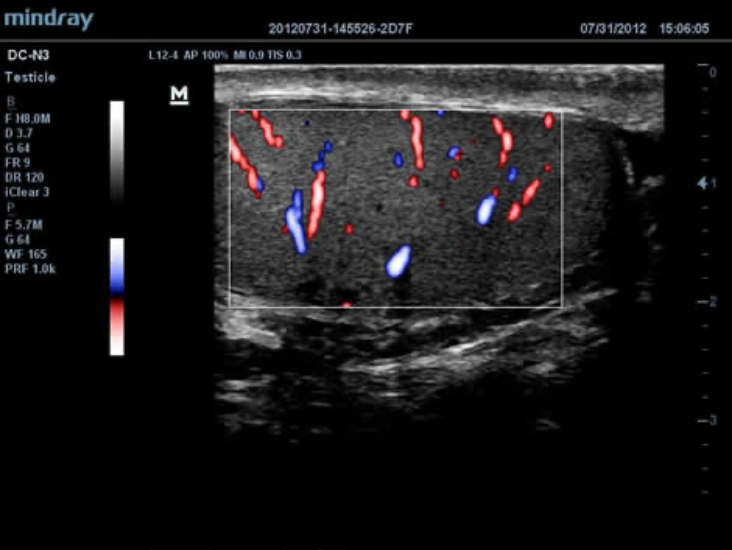

DC-N3 PRO

DC-N3 PRO? ??? ??? ??, ???, ???? ?? ???? ??? ?? ?????. ?? ??? DC-N3 PRO? ??? ??? ?? ??? ??? ???? ???? ??? ????? ??????. ???? ?? ???? ???? ?? ??? ???? ???? ???? ?? ? ????.

DC-N3 PRO? ??? ??? ?? ??? ??? ????? ?? ???? ???? ??? ?? ??? ??? ?? ???? ??? ?????. ?? ??? ??, ???, ??? ?? ??? ??? ??? ?????. ????? ???? ???? ????? ??? ???? ??? ?? ?? ?? ??? ??? ???? ??? ?????.